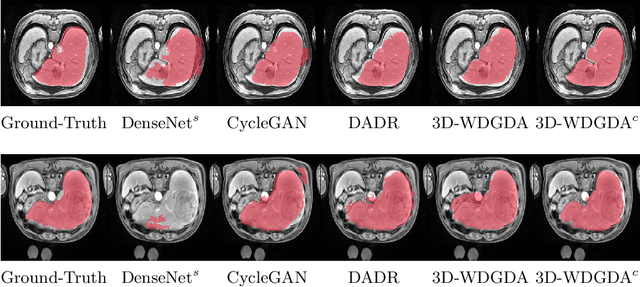

Abstract:Deep neural networks have shown exceptional learning capability and generalizability in the source domain when massive labeled data is provided. However, the well-trained models often fail in the target domain due to the domain shift. Unsupervised domain adaptation aims to improve network performance when applying robust models trained on medical images from source domains to a new target domain. In this work, we present an approach based on the Wasserstein distance guided disentangled representation to achieve 3D multi-domain liver segmentation. Concretely, we embed images onto a shared content space capturing shared feature-level information across domains and domain-specific appearance spaces. The existing mutual information-based representation learning approaches often fail to capture complete representations in multi-domain medical imaging tasks. To mitigate these issues, we utilize Wasserstein distance to learn more complete representation, and introduces a content discriminator to further facilitate the representation disentanglement. Experiments demonstrate that our method outperforms the state-of-the-art on the multi-modality liver segmentation task.